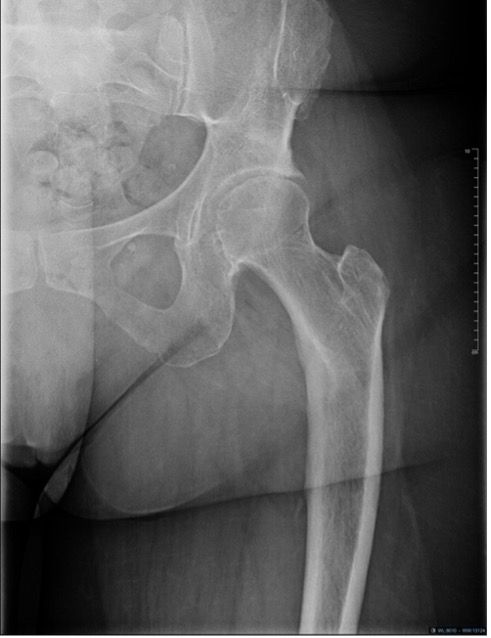

Stress shielding and bone changes

Stress shielding is a phenomenon caused by uneven distribution of mechanical stresses to the femur, which, when they predominate at the distal part of the stem, generate a pattern of bone changes consisting of distal bone hypertrophy (due to excess stresses) and proximal osteolysis (due to a lack of stresses). Several biomechanical studies report stress shielding to be reduced by using short stem metaphyseal implants [7]. This compressive load transfer tends to happen at the distal end of the stem for short stems, taking the load off the proximal femur. Filling of the medullary canal (ratio of stem diameter to intramedullary diameter) for conventional straight stems increases from the proximal to distal end. This observation is all the more marked when the femur has an intramedullary “champagne flute” appearance (Dorr A).

Bieger [8]reported a more physiological proximal transfer of forces with the Optimys stem than with a straight stem. Karachalios [8] noted that a calcar-guided short stem offered better transmission of proximal loads, which probably reduces these phenomena of stress-shielding, although the causes are multifactorial, depending in particular on the varus/valgus positioning of the stem. While it may reduce the rate, fitting a short stem does not guarantee an absence of stress shielding. Kutzner [10] reported in 2016 only 4.4% cortical thickening and 3.9% proximal bone resorption. A recent densitometry study moreover confirmed the decrease in stress shielding and good peri-prosthetic bone preservation for short stem implants [11]. The radiographic image shown in Figure 10 emains rare in our daily practice.